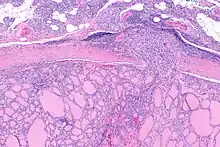

| Micrograph of follicular thyroid carcinoma showing a location where the cancer grows through the fibrous capsule. H&E stain. | |

It is impossible to distinguish between follicular adenoma and carcinoma on cytological grounds. If fine needle aspiration cytology (FNAC) suggests follicular neoplasm, thyroid lobectomy should be performed to establish the histopathological diagnosis. Features sine qua non for the diagnosis of follicular carcinoma are capsular invasion and vascular invasion by tumor cells. Still, focuses of the capsular invasion should be carefully evaluated and discriminated from the capsular rupture due to FNA penetration resulting in WHAFFT (worrisome histologic alterations following FNA of thyroid).